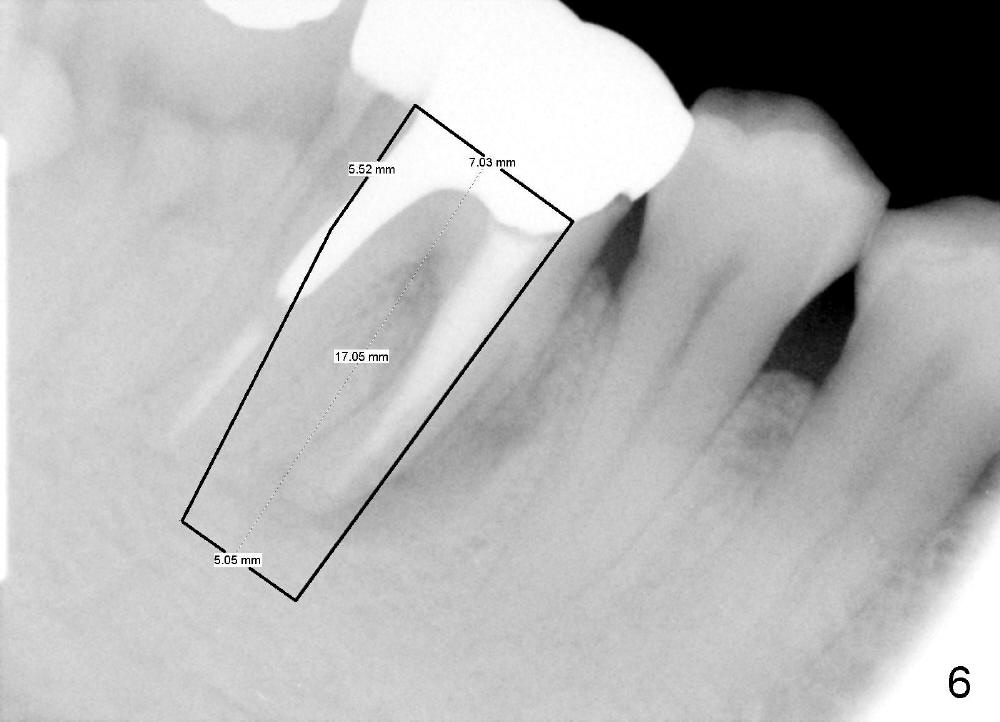

Section the septum mesiodistally with thin osteotomes so that drills and/or rounded osteotomes (Fig.4 red long arrow) will stay in the middle or mesial portion of the septum, while a part of the septum is being pushed distally (open arrow). When larger drills or osteotomes (Fig.5 thicker red long arrow) are being used, more of the septum is being pushed distally (open arrow). A 7x17 mm implant is expected to be placed in the middle of the septum or slightly into the mesial socket (Fig.6). Where does this implant end up?